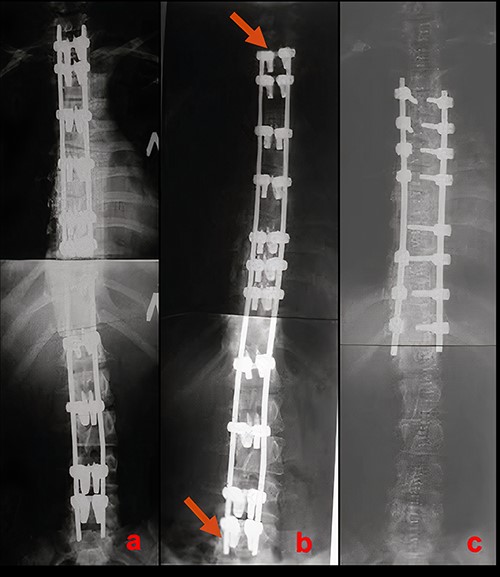

Due to rapid deformity progression and incomplete skeletal maturity, 2-stage surgical treatment was elected. At the first stage, posterior correction and T1-L5 instrumentation using the LSZ growing system were performed. The intervention lasted 125 min. Blood loss amounted to 240 ml. The postoperative period was uneventful. Radiographs on postoperative Day 5 demonstrated 83% correction (Fig. 3a). The immediate postoperative sitting height was 75 cm.

Radiographic results of surgical treatment. (a) AP X-rays of the patient’s spine in standing position after the 1st stage of surgical treatment on the 5th day after surgery. Residual deformity of the spine was 15°. (b) AP X-ray of the patient’s spine in a standing position 4 years after surgery. Growth of the spine and the associated shortening of the free upper and lower ends of the plates can be observed (red arrows). (c) AP X-ray of the patient’s spine after the 2nd stage of surgical treatment. The angle of residual deformity is < 5°.

At a 4-year follow-up at the age of 16, the spine grew by 5 cm. The patient’s sitting height was 80 cm. Shortening of the free ends of the plates at the upper and lower ends of instrumentation, associated with the continued growth of the spine could be clearly visualized (Fig. 3b).

As the second stage of surgical treatment, the LSZ system was removed and definitive T4-T12 instrumentation was performed. The duration of the surgery was 203 min. Blood loss amounted to 450 ml. Postoperative radiographs demonstrated 94% deformity correction (compared with deformity before index surgery) (Fig. 3c). The patient was mobilized on Day 2.